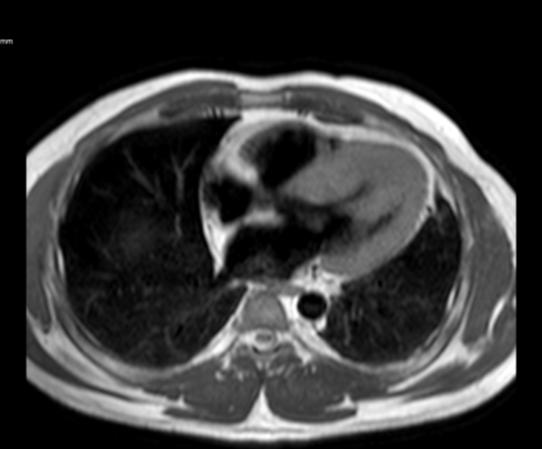

Figure 1: Vista coronal de resonancia magnética cardíaca IVS engrosamiento 3,0cm e infiltración fibrosa septal.

INTRODUCCIÓN

• La resonancia magnética cardíaca

Cardiovascular Disease Fellowship Program, St. Figure 2: Vista sagital de la resonancia magnética cardíaca IVS engrosamiento de 3,0 cm e infiltración fibrosa septal.

posterior mostró un engrosamiento del tabique interventricular de 3,0 cm, así como una infiltración fibrosa del tabique confirmando el diagnóstico de MCH.

Figure 3: Vista axial de resonancia magnética cardíaca IVS engrosamiento 3.0cm e infiltración fibrosa septal.